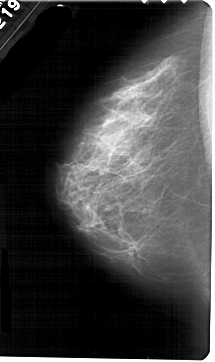

A_1614_1.RIGHT_CC

RIGHT_CC LINES 5491 PIXELS_PER_LINE 2791 BITS_PER_PIXEL 12 RESOLUTION 43.5 OVERLAY

FILE: A_1614_1.RIGHT_CC.OVERLAY

TOTAL_ABNORMALITIES 1

ABNORMALITY 1

LESION_TYPE CALCIFICATION TYPE PLEOMORPHIC DISTRIBUTION CLUSTERED

ASSESSMENT 4

SUBTLETY 1

PATHOLOGY MALIGNANT

TOTAL_OUTLINES 1

BOUNDARY